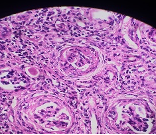

HISTOPATHOLOGY

What is the lesion seen in this section ?

Ans to previous : (August 2025)

Tumour embolus in a lymphatic channel.